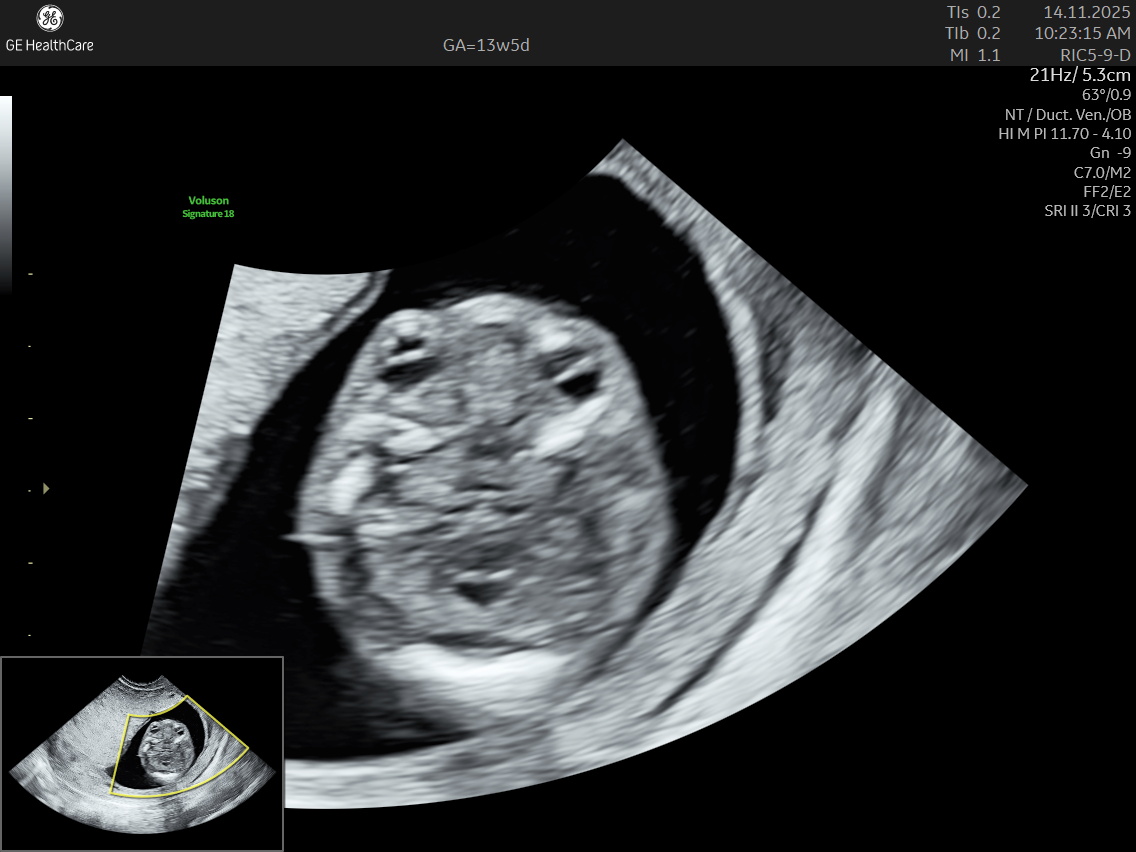

- Other major structural fetal abnormalities such as duodenal atresia, body stalk anomaly, and multisystem abnormalities including acrania and kyphoscoliosis.

Although the NT scan is mainly a screening tool and not diagnostic on its own, it can identify about 50% of major fetal abnormalities when combined with other assessments like blood tests and detailed ultrasound. The scan also helps to screen some basic anatomical structures during the first trimester, especially the fetal heart anatomy, brain, face, spine, stomach, abdominal wall, kidneys, bladder, and extremities to varying degrees depending on gestational age and maternal factors.